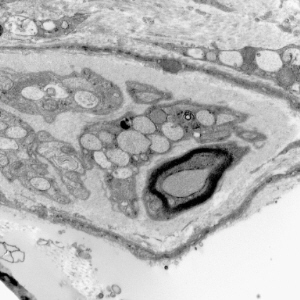

Immunohistochemistry and ultrastructural findings

- immunohistochemistry for lysosomal storage disorders not well developed

- ultrastructural findings useful in diagnosis

- lysosomal vacuoles with ill-defined contents

- may see glycogen granules

- "zebra bodies" in MPS

- lipopigments in the form of curvilinear profiles (like in NCL)

Lysosomal vacuoles and zebra bodies in mucopolysaccharidosis (mitral valve)